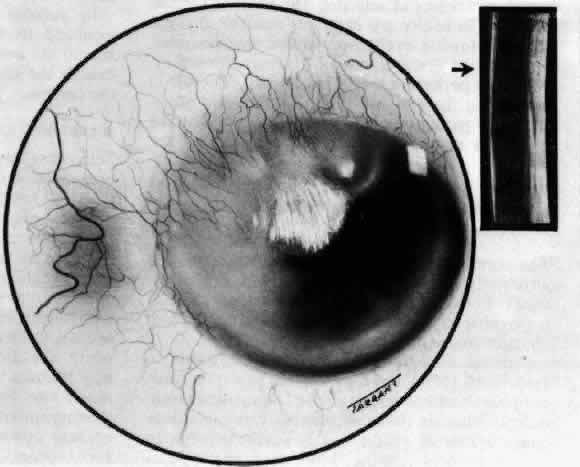

Simple and nodular episcleritis differ in their clinical courses, but in both the edema and infiltration are entirely within the episcleral tissues. The sclera is not involved. The maximum congestion is in the superficial episcleral network, with some slight congestion of the conjunctival vessels and deep episcleral vessels (Fig. 10). The intraocular structures are not involved in either variety, nor is the visual acuity affected. Anterior segment fluorescein angiography reveals a normal vascular pattern but a very rapid flow rate, with the whole transit of the dye being completed within 2 or 3 seconds (Figs. 11 and 12).

Fig. 10. Maximum congestion in the superficial vascular plexus in episcleritis. The conjunctival and deep episcleral networks are separated from the deep plexus by edema and infiltration in the episcleral tissue. (Watson PG, Hayreh S, Awdry P: Episcleritis and scleritis. Br J Ophthalmol 52(3):278–279, 1968)

Fig. 11. Anterior segment fluorescein angiogram of a 45-year-old woman with simple episcleritis. At first transit of dye, all the vessels are dilated and filling simultaneously. However, the vascular pattern is not disturbed.

Fig. 12. Angiogram of the same 45-year-old woman in Figure 11 one second later. Within 1 second, all the vessels are filled and there is even, venular filling except in the deep episcleral plexus. This is the rapid filling pattern seen in all forms of episcleritis and in diffuse anterior scleritis.